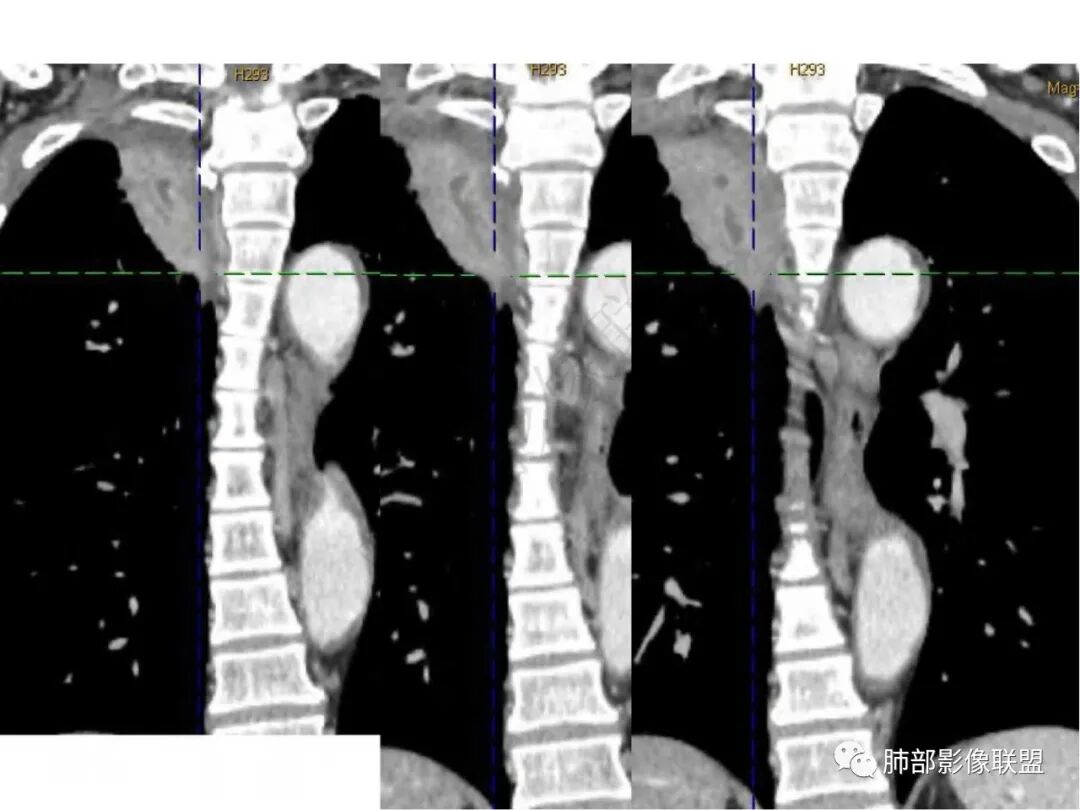

放射线:右肺尖不规则肿块,有分叶毛刺,有胸膜栽赃,冠状位可见支气管粘液栓,矢状位病灶呈外朝内沿支气管分叉角生长,强化明显,考虑腺癌,鉴别炎性肉芽肿病变。

良孑:右上肺占位,有平直及u型凹陷,其内见粘液拴及虫蚀样坏死空洞,不均匀强化,坏死空洞环状强化,失状位病灶沿支气管长轴生长呈爬行征样改变,综合考虑为炎性肉芽肿,首选TB,鉴别诊断鳞癌

琦遇:病灶沿右肺上叶尖段走形实变,远端大近端小,边缘平直收缩为主,近端尖段分支部分截断,内部可见扩张的支气管粘液栓,增强后明显强化,比较均匀,内部血管走形自然,与纵膈胸膜及后胸膜呈糊墙样,未见栽桩,纵膈未见明显肿大淋巴结 综合分析考虑炎性病灶可能性大 (IMT、OP、结核、慢性炎症) 因患者年龄大、老烟民 警惕恶性可能(淋巴瘤、鳞癌) 临床上下一步做支气管镜看看

张延军:右肺上叶条片影,边缘以平直及凹陷为主,病灶内见管状低密度影,延迟后边缘有强化,近段气管截断,血管走形自然,整体外宽内窄,考虑炎性肉芽肿,结核不除外